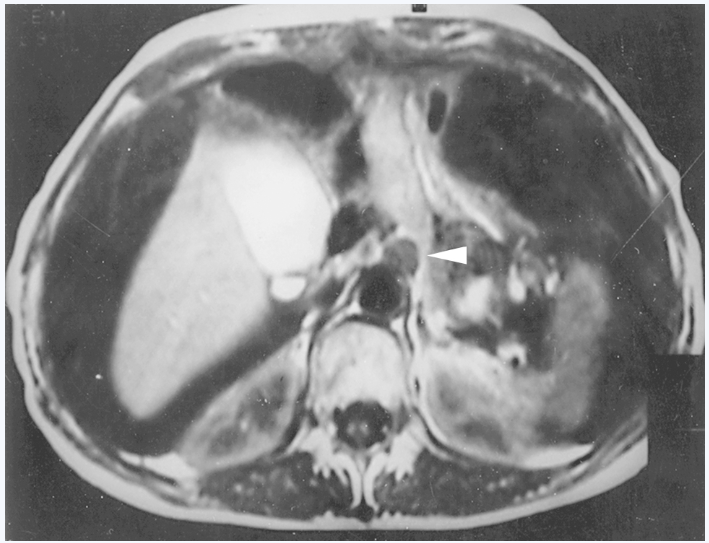

MRI检查可显示不同大小的原发肿块;胃壁增厚;也能估计肿瘤在胃肠道壁中浸润的深度和肿瘤的腔外侵犯(图12)。胃腺癌通常在T1加权像上与正常胃黏膜等信号,T2加权像上略高于胃黏膜信号;而在弥漫浸润型癌中,由于纤维组织存在,T1和T2加权像上都使信号减弱。增强后T1加权像上则呈不均匀强化。正常胃壁低信号外带的不规则或缺失均提示胃癌的浆膜外已受侵犯。MRI的Gd-DTPA增强和脂肪抑制图像能显示强化的转移性淋巴结;鉴别淋巴结与血管影;发现肝转移灶(图13)。

图12

图12 胃窦部癌

横断面增强后T2WI图像显示胃窦后壁略高且不均匀癌块侵及胰头部